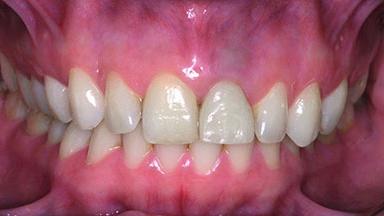

Replacement of a Perforated Upper Left Central Incisor: Early Placement of an RC Bone Level Implant

A 28-year-old patient presented at her general dentist’s office and complained about the appearance of her tooth 21. The patient had a history of trauma to this tooth. Endodontic treatment had been performed in the past and a crown placed on the tooth. A procedure to replace the old crown was performed by her dentist; however, a perforation on the middle third of the root occurred, and extraction of tooth 21 was suggested. Upon clinical and radiographic examination of the patient, who had been referred to us, replacement of tooth 21 by a dental implant appeared to be indicated.